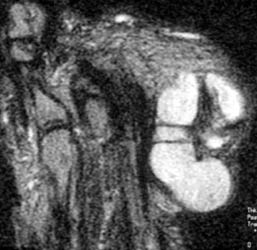

47 year old male with a 6 x 3.5 cm lobulated mass along plantar medial aspect of the 1st toe, which is hypointense on T1W and hyperintense On T2W images. Scattered small foci of hypointensity, representing calcifications is present on all the sequences. The soft tissue mass with small calcifications is also seen on the plain radiograph.